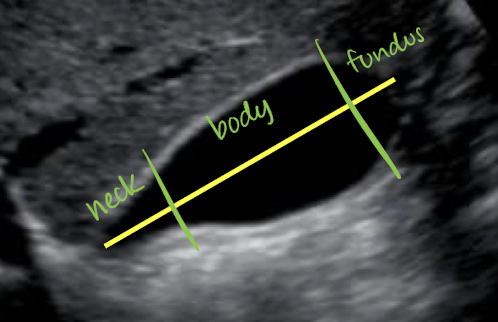

GB parts and info

parts: neck (superior portion), body, and fundus (inferior portion; close to bowel)

around 9 cm from neck to fundus

GB >12 cm is considered hydrops

holds up to 40 mL of bile

supplied by cystic artery